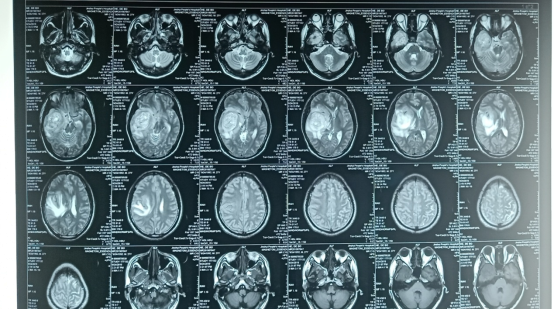

20190927郑州金水医院

20190927郑大一附院:右侧颞叶巨大占位,考虑胶质瘤。

术后MRI:20191005郑大一附院:“右颞部占位切除术”后改变。

放化疗后MRI:20191020西安交大